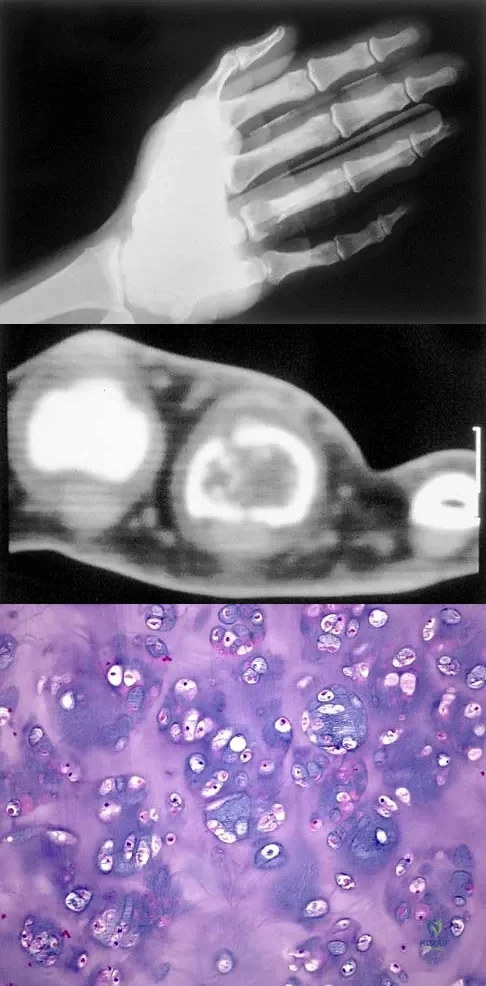

A 30-year-old woman has pain in her right hand. The radiograph, CT scan, and biopsy specimen are seen in Figures 38a through 38c. What is the most likely diagnosis?

A 10-year-old boy has a painful thigh mass. A radiograph, MRI scan, and biopsy specimen are shown in Figures 42a through 42c. What is the most likely diagnosis?